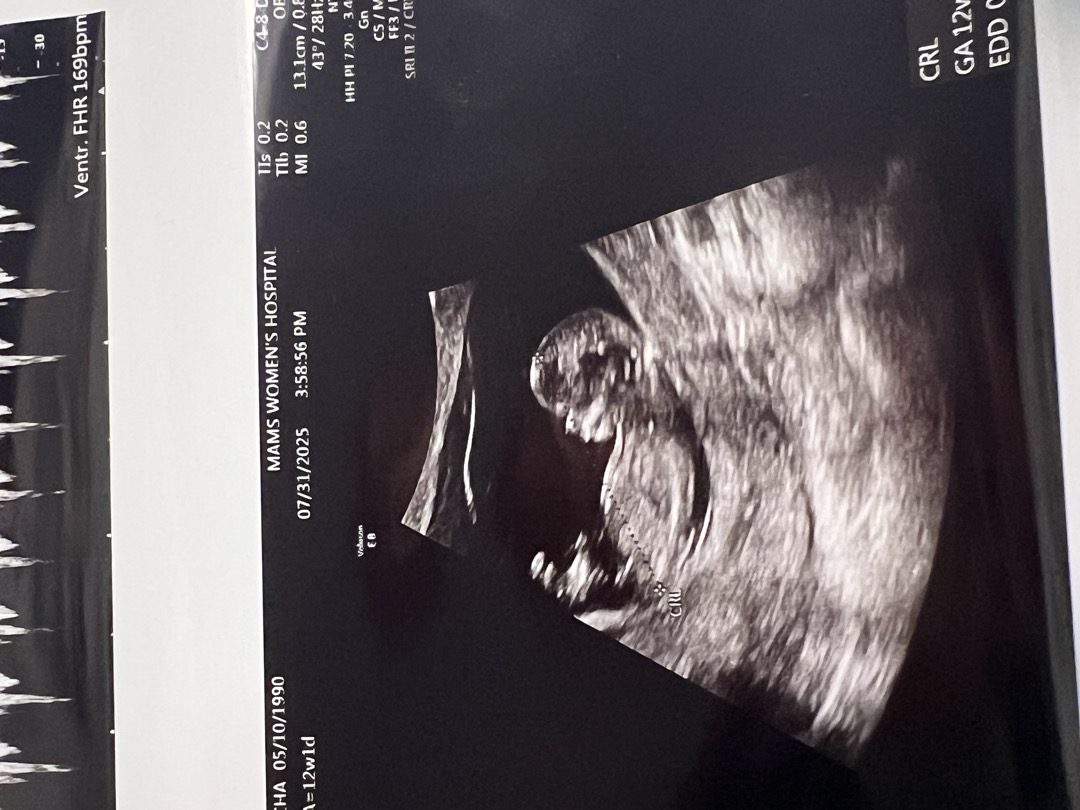

12주차 각도법봐주세요~~

엎드려있어서 옆모습 이거하나 나왔는데 알수있을까요????

아들이요!

아들같아요